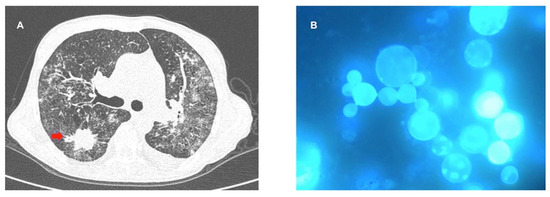

- De Freitas, R.S.; Dantas, K.C.; Garcia, R.S.P.; Magri, M.M.C.; de Andrade, H.F. Paracoccidioides brasiliensis causing a rib lesion in an adult AIDS patient. Hum. Pathol. 2010, 41, 1350–1354. [Google Scholar] [CrossRef] [PubMed]

- Radisic, M.V.; Linares, L.; Afeltra, J.; Pujato, N.; Vitale, R.G.; Bravo, M.; Dotta, A.C.; Casadei, D.H. Acute pulmonary involvement by paracoccidiodomycosis disease immediately after kidney transplantation: Case report and literature review. Transpl. Infect. Dis. 2017, 19, e12655. [Google Scholar] [CrossRef] [PubMed]

- Lima, T.C.; Bezerra, R.O.F.; Siqueira, L.T.; Menezes, M.R.; Leite, C.; Porta, G.; Cerri, G.G. Paracoccidioidomycosis in a liver transplant recipient. Rev. Soc. Bras. Med. Trop. 2017, 50, 138–140. [Google Scholar] [CrossRef] [PubMed]